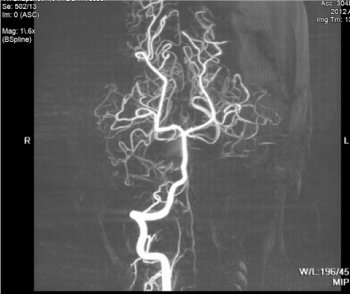

The patient’s hospital stay was uneventful and managed medically. During his stay in the ICU, the patient received an MRI for more detailed imaging, which demonstrated the extent of the hematoma (Figure 2 and 3).

Figure 3. MR angiogram is unremarkable